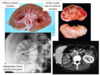

Which stain is used to view Chronic Glomerulonephritis?

What’s seen?

- Massone trichrome stain

- Showing complete replacement of all glomeruli by blue-staining collagen